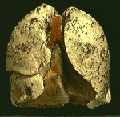

Αθήνα: Αμερικανοί ερευνητές, χρησιμοποιώντας γενετικές τεχνικές, ανακάλυψαν μια μέθοδο να εντοπίζουν εκείνους τους καπνιστές, που αντιμετωπίζουν τον μεγαλύτερο κίνδυνο να εμφανίσουν καρκίνο των πνευμόνων.